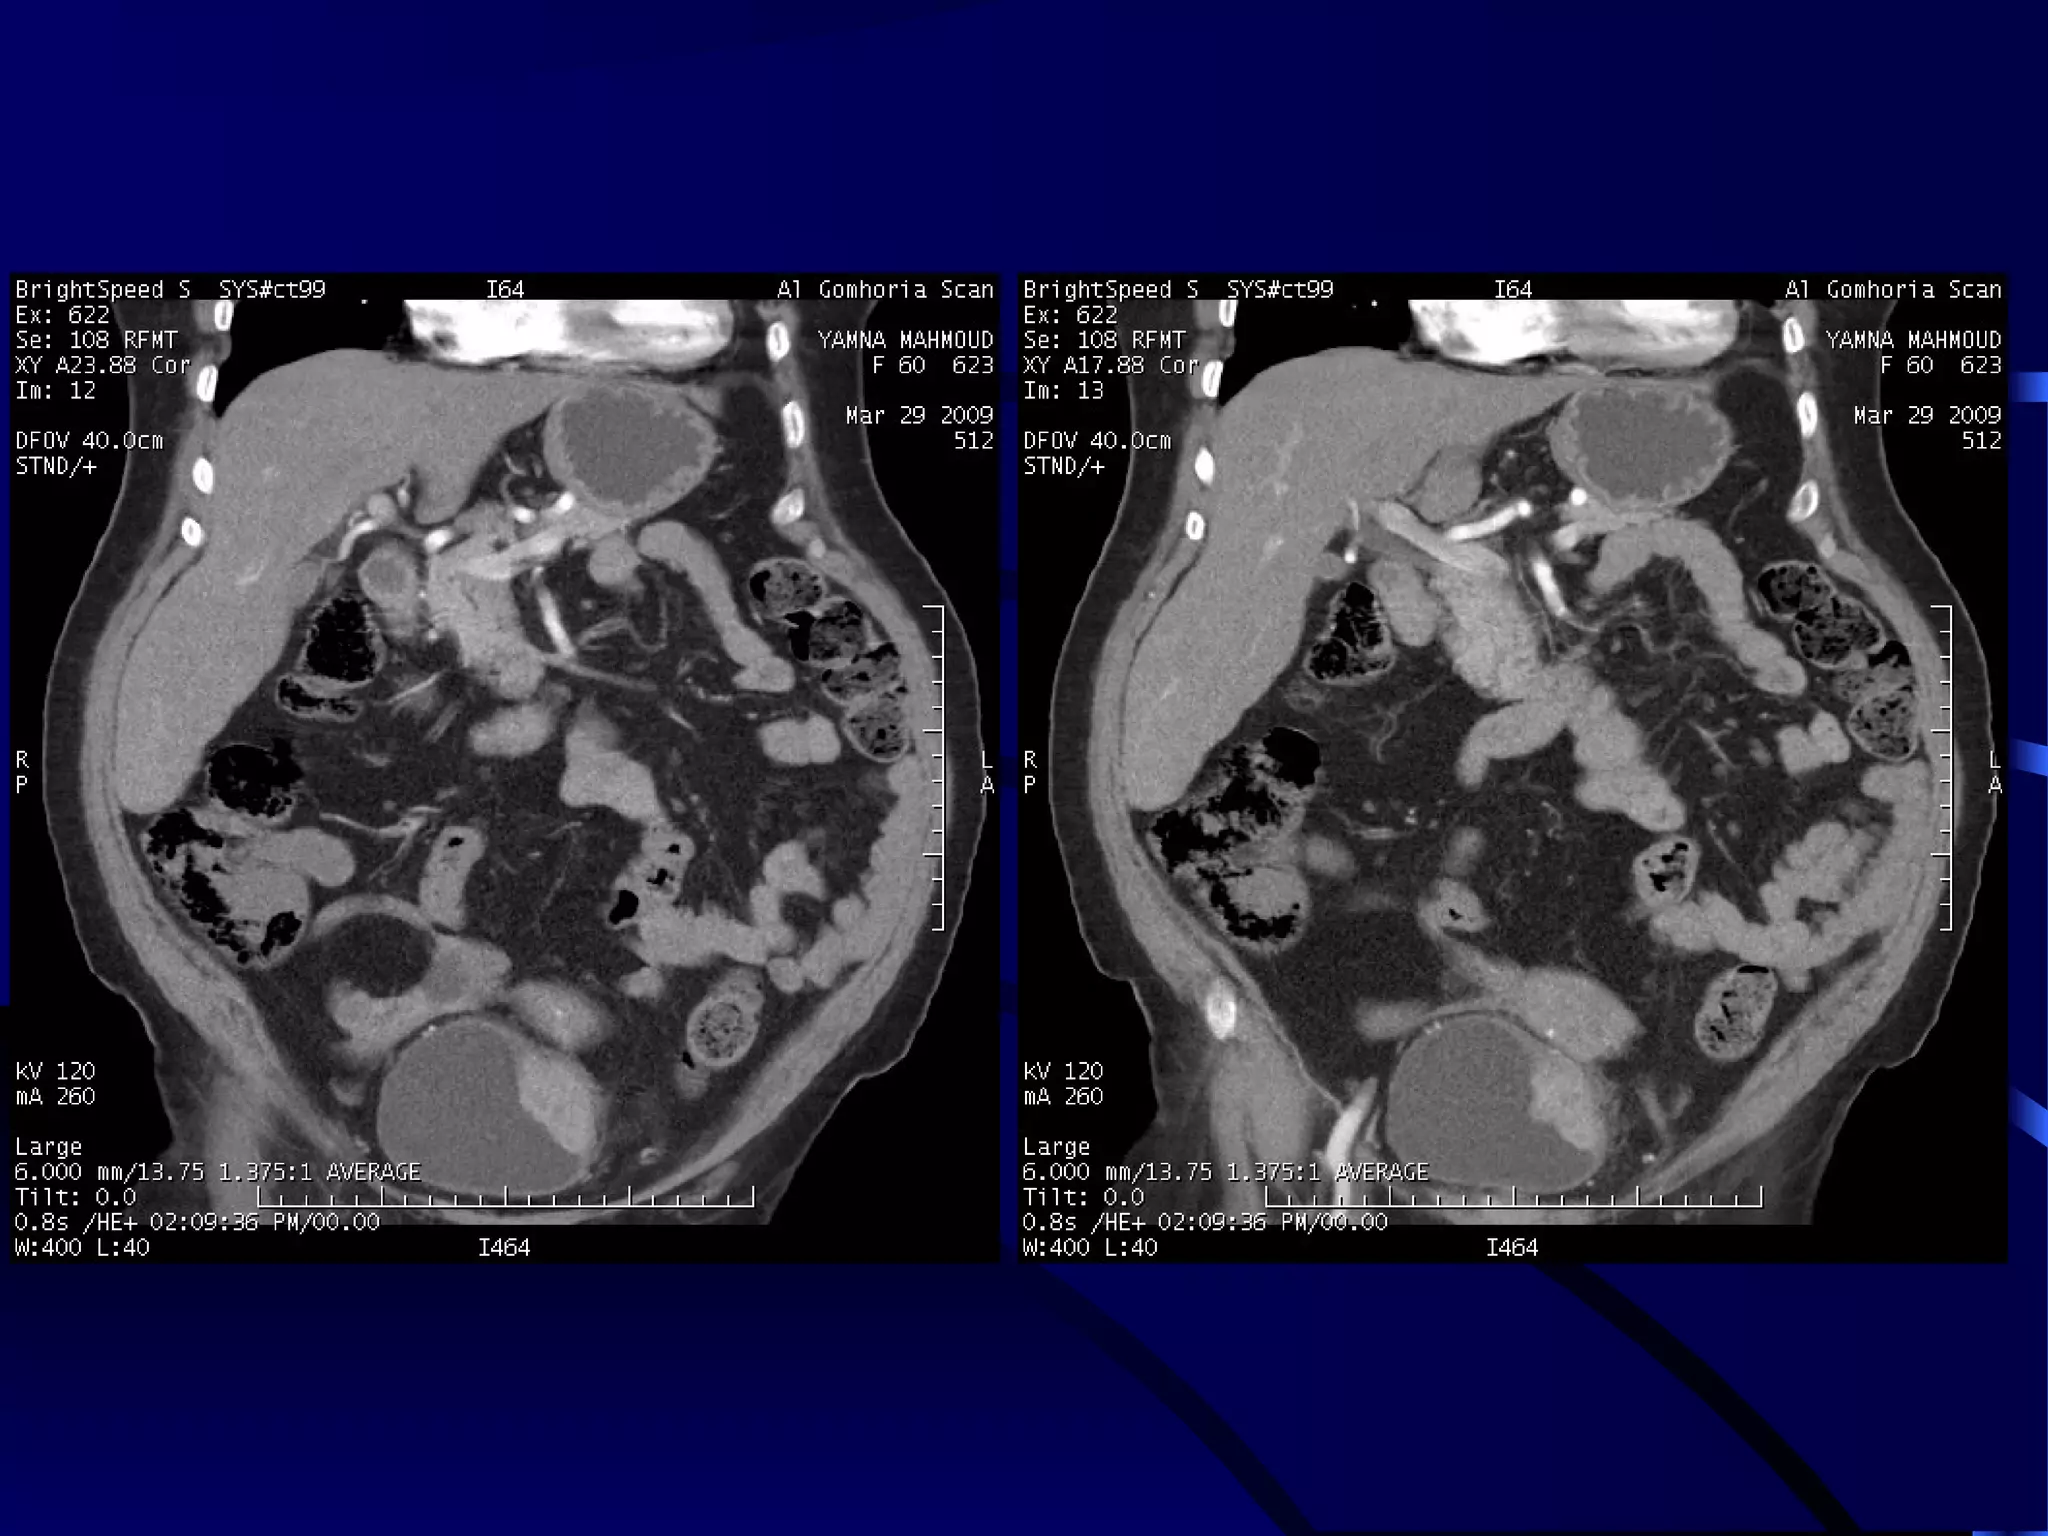

CASE (10)

MALIGNAT SUPRARENAL MASS

WITH LIVER METASTASES

DISPLACED LEFT KIDNEY WITH

DOUPLEX RIGHT COLLECTING SYSTEM